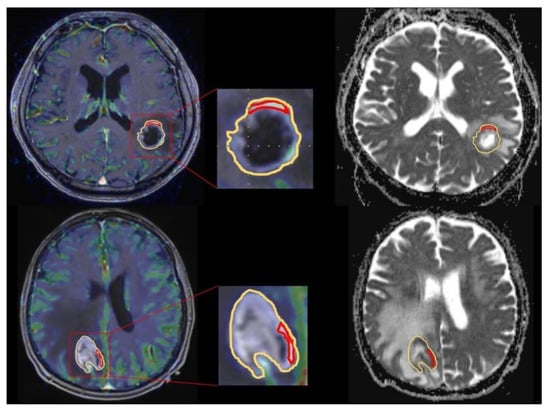

3.2. DWI Results

3.3. CBV Results